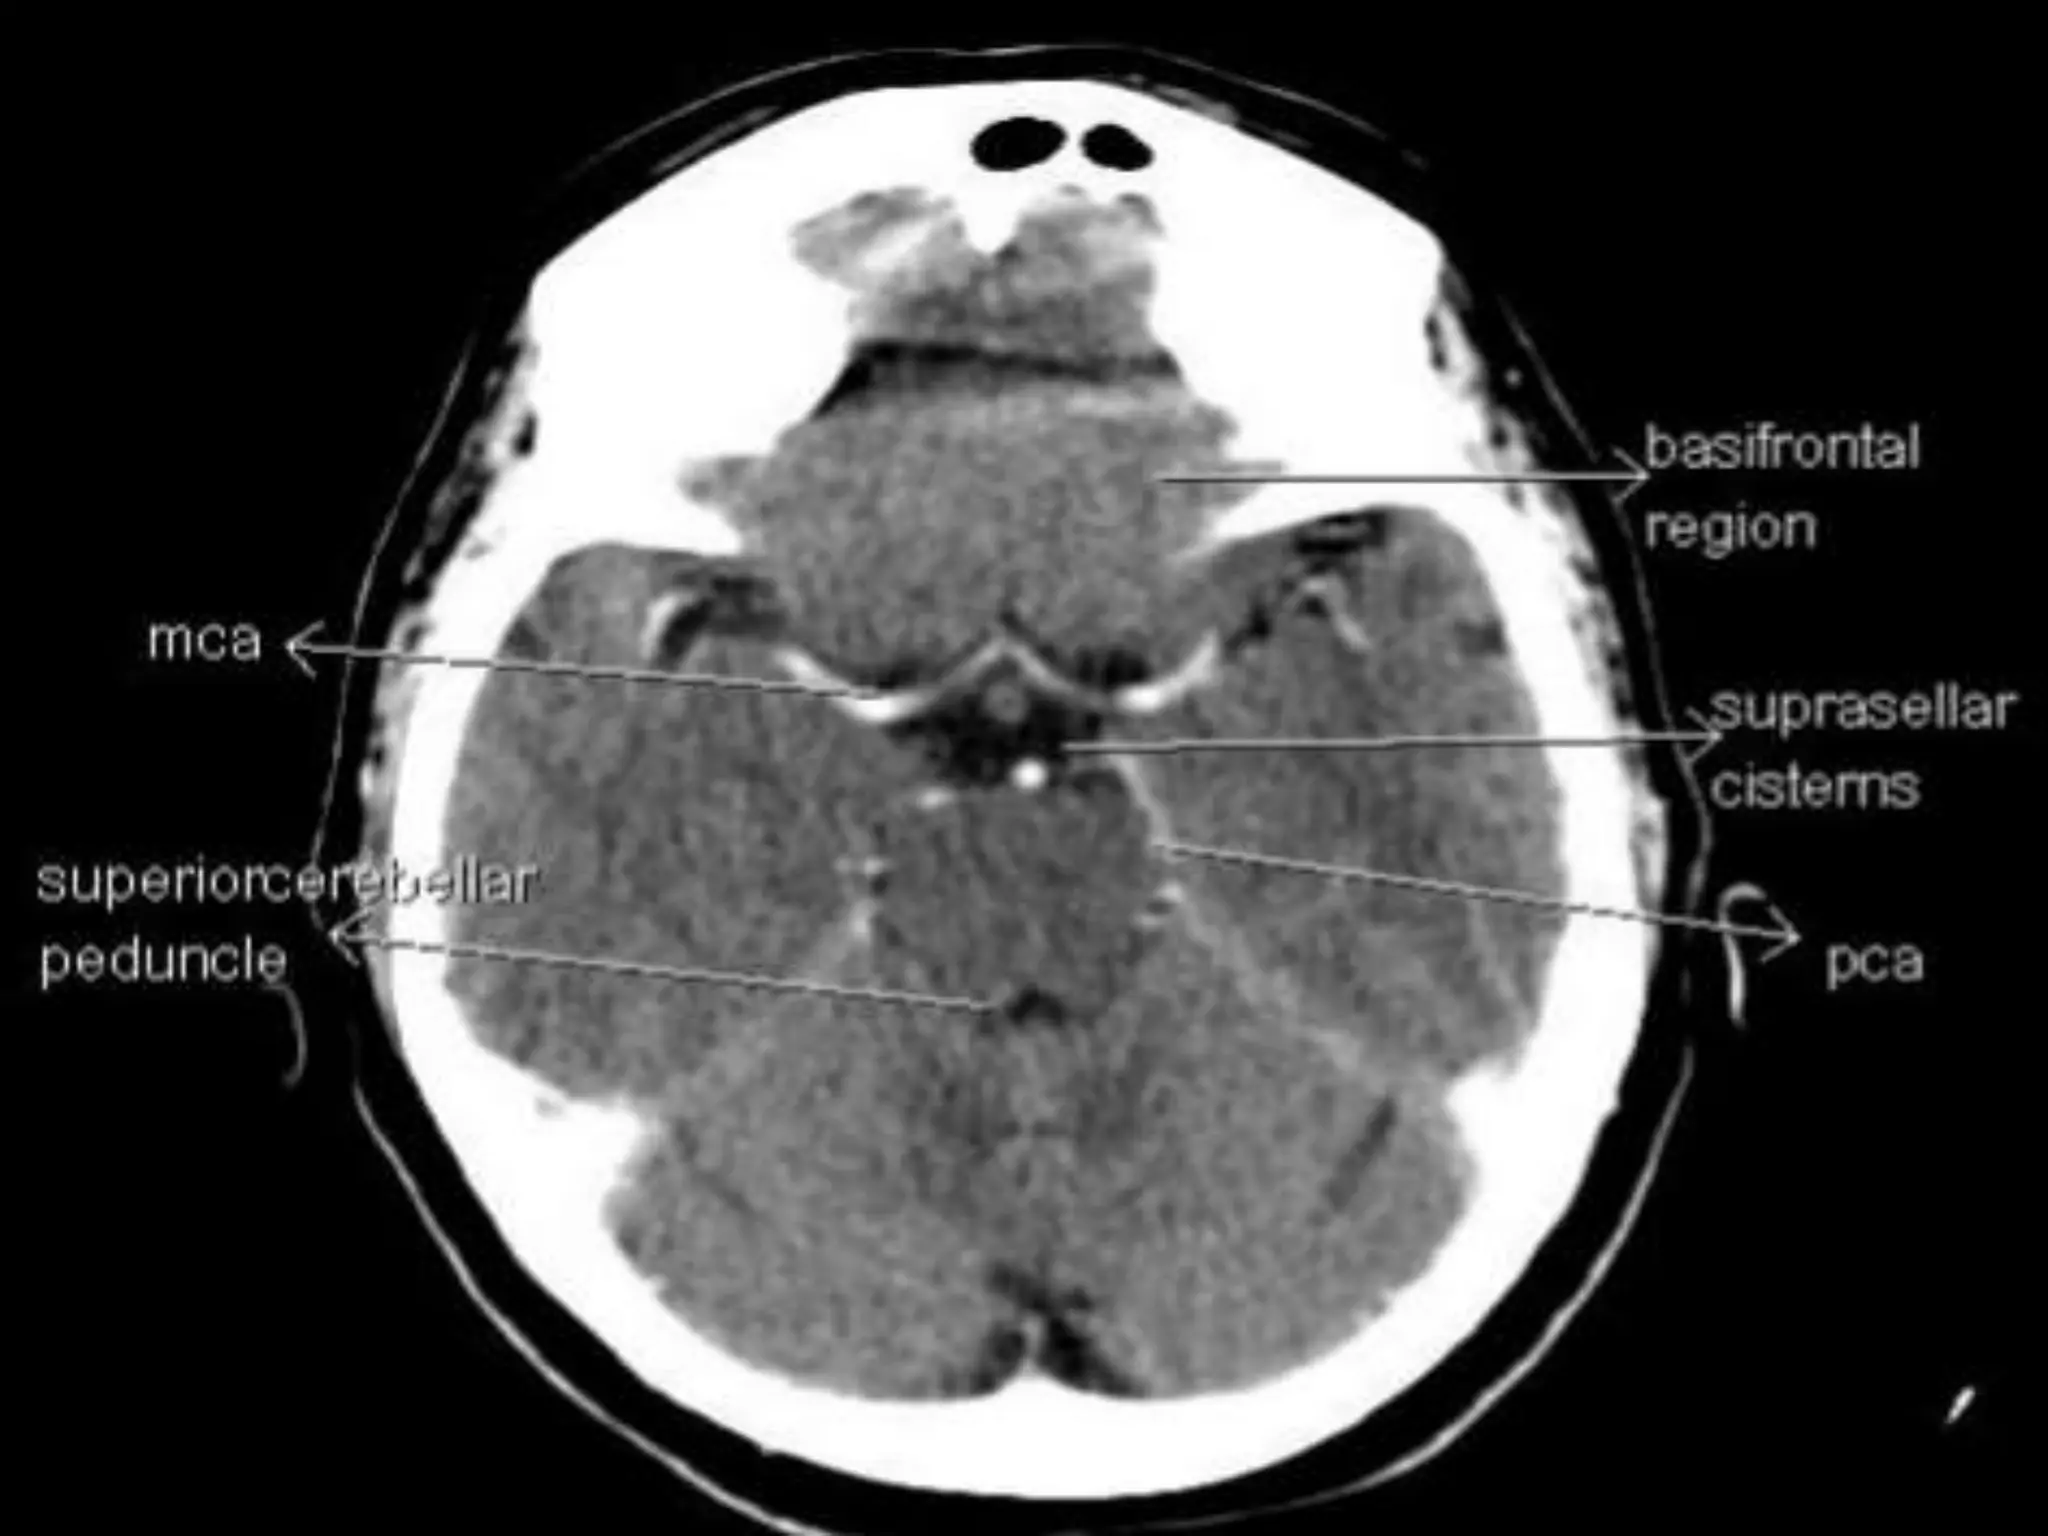

Sectional Anatomy: NormalAxial CT and MRI Anatomy. On CT and MR scans, the brain has been briefly viewed in infratentorial and supratentorial sections, as described below. CT scans are performed with a 15- to 20-degree angulation to the canthomeatal line at 8-mm increments. MRI scans are generally obtained parallel to the AC-PC line in the axial plane with 6-mm slice thickness. Using the sagittal view, the coronal sections are acquired parallel to the brain stem, and the sagittal sections are obtained perpendicular to the axial section. On MRI studies, cranial nerves IX and X can be demonstrated at this level because they emerge from the postolivary sulcus. The posterior aspect of the cerebellar hemispheres is outlined by the inferior portion of the cisterna magna.